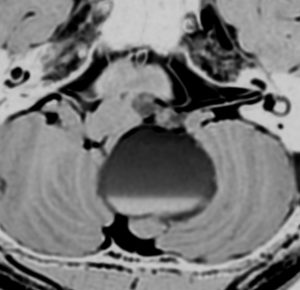

症例:延髄軟膜下 のもの subpial schwannoma in the medulla oblongata

40代男性です。咽せる,頚部痛という迷走神経症状で発症し,小脳失調がでてから腫瘍が発見されました。ある病院で第4脳室と脳槽内ののう胞性部分を摘出され,残存腫瘍摘出の目的で紹介されました。残った腫瘍は迷走神経根の腹側の延髄内部に食い込み,延髄軟膜下 subpial に主体がありました。nearly complete resectionをして経過を見ています。術後は嚥下障害が悪化したのですがかなり回復して,嗄声はなく自宅で食事をする日常生活にもどれました。